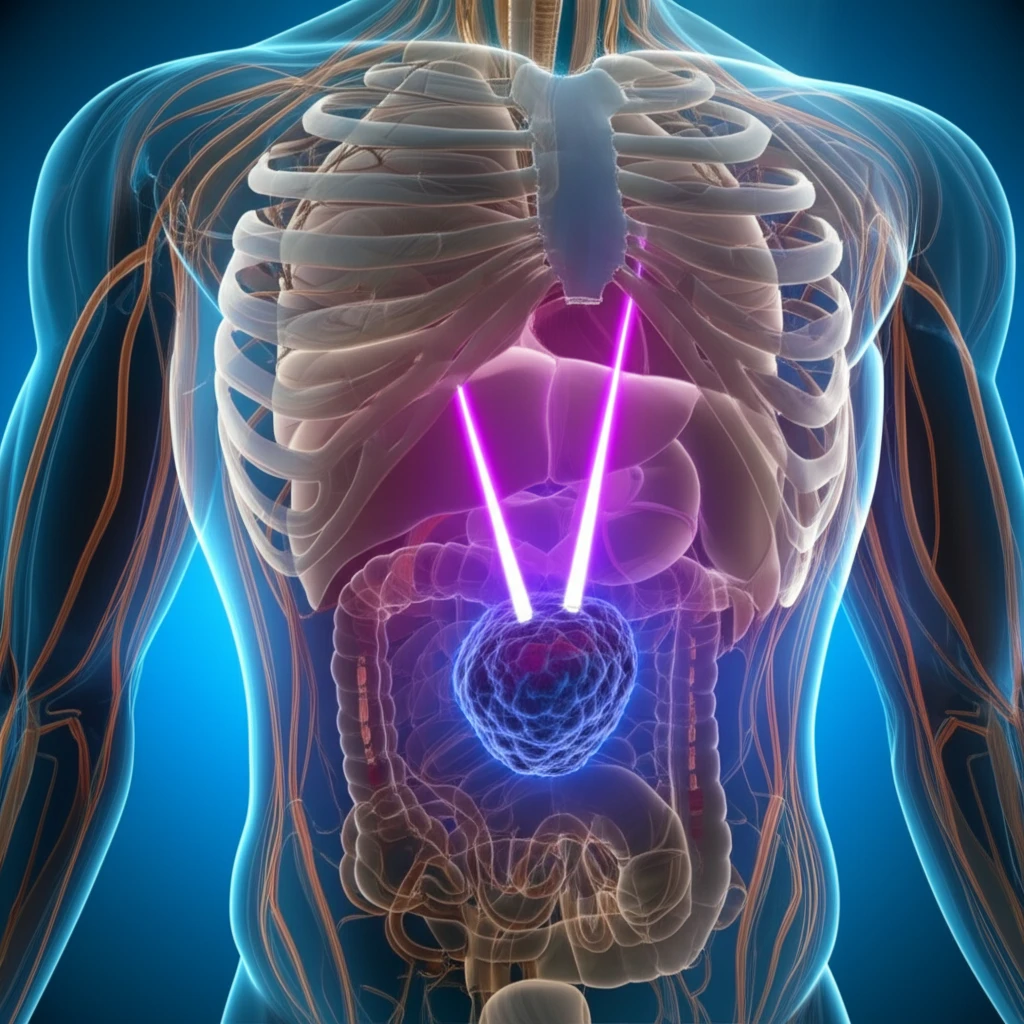

Stereotactic Body Radiation Therapy (SBRT) has emerged as a significant advancement in cancer treatment, offering a precise and effective approach to targeting tumors while minimizing damage to surrounding healthy tissues. This technique is particularly valuable for patients with localized tumors who may not be suitable candidates for surgery or prefer a non-invasive treatment option.

Two key areas where SBRT has shown considerable promise are in the treatment of lung and prostate cancer. In lung cancer, SBRT is used for both primary early-stage non-small cell lung cancer (NSCLC) and local relapses following surgery. For prostate cancer, SBRT offers an alternative to traditional radiation therapy, with the goal of delivering high doses of radiation to the tumor while sparing the rectum and other nearby organs.

This article will explore the latest research on SBRT for lung and prostate cancer, highlighting the benefits, challenges, and ongoing efforts to optimize treatment protocols. We will delve into the importance of credentialing in lung SBRT, as well as the dosimetric considerations for achieving optimal rectal sparing in prostate cancer SBRT. Understanding these aspects is crucial for healthcare professionals and patients alike, as SBRT continues to evolve and play an increasingly important role in cancer management.